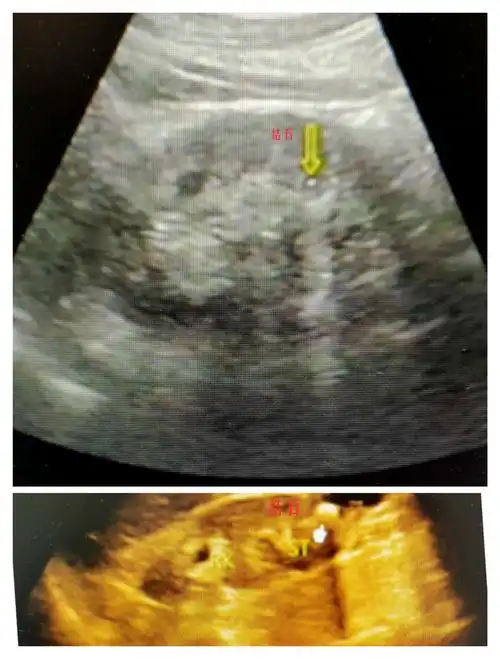

怀孕五个月了查出右边肾结石4x2mm是有多大?会影响胎儿吗?

青海省康乐医院超声科邀您一起了解:超声下的肾结石.

晚上值班一开始我真没看见这个肾结石